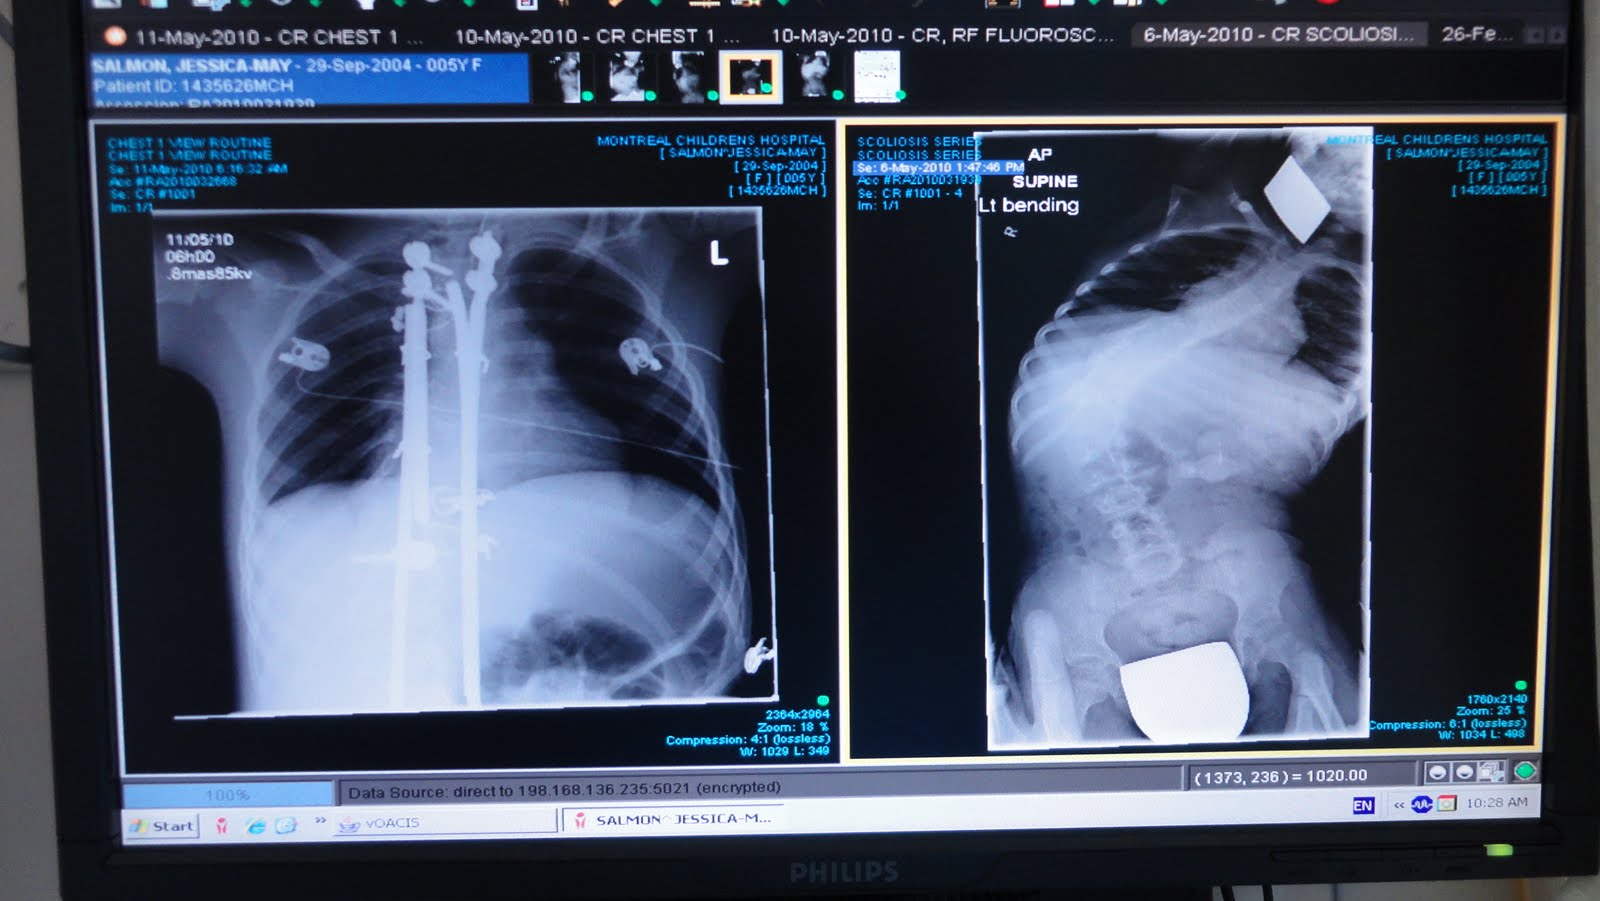

Look how STRAIGHT her back is!!! We had to change her bandage because when they were taking out the breathing tube, she had vomitted and it ran down her neck and back. This gave us a good chance to see her scar. The surgeon did a wonderful job sewing her up. There was no blood and it looked very healthy.

We had a chance to check out the xrays that they took early this morning. The rods are very overwhelming but the important part is how straight her back looksand how much room her organs will have to grow and flourish!! The before and after pictures are astonishing....

Today we spent the day at Montreal Children's Hospital. Jessica's had some blood work done, visit from a physio therapist, x-rays of her back, appointment with the respiralogist and a tour of the recovery room where she will be staying.